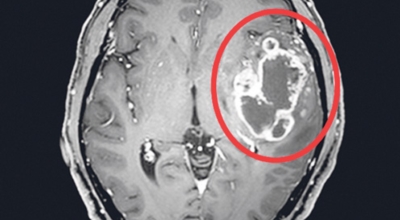

4. 뇌종양 초기증상 - 교모세포종의 문제

뇌종양 초기증상 여섯 번째는 교모세포종의 문제입니다. 가장 흔한 뇌종양은 수막종이며 종양의 크기나 위치에 따라 수술이 필요하지 않을 수 있지만 청각 신경초종은 이명을 나타나게 할 수 있고 심한 경우 안면 마비, 경련 및 통증을 유발할 수 있지만 뇌종양은 생존을 좌우하게되는 교모세포종 문제가 뒤늦게 생기는 것으로 주의가 필요한 이유입니다.